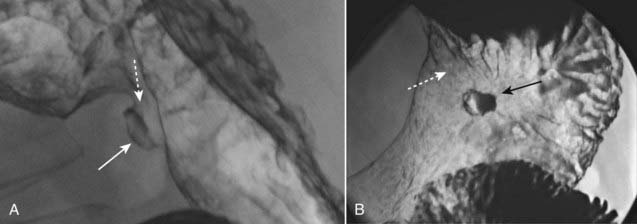

Figure 18-15 Polyp on virtual colonoscopy.

Virtual colonoscopy utilizes CT scanning of the abdomen to allow for the three-dimensional reconstruction of the appearance of the inside of the bowel lumen without the use of an endoscope. A polyp in the descending colon (solid black arrow) is seen as a distinct mass, while the normal haustral folds (solid white arrows) are ridgelike structures present throughout the large bowel.

image Virtual colonoscopy is a technique made possible by newer, faster CT and MRI scanners and complex computer algorithms that allow for the three-dimensional reconstruction of the appearance of the inside of the bowel lumen including time-of-flight (motion) displays without the use of an endoscope. Virtual colonoscopy also allows for visualization of the other abdominal structures outside of the colon (Fig. 18-15).